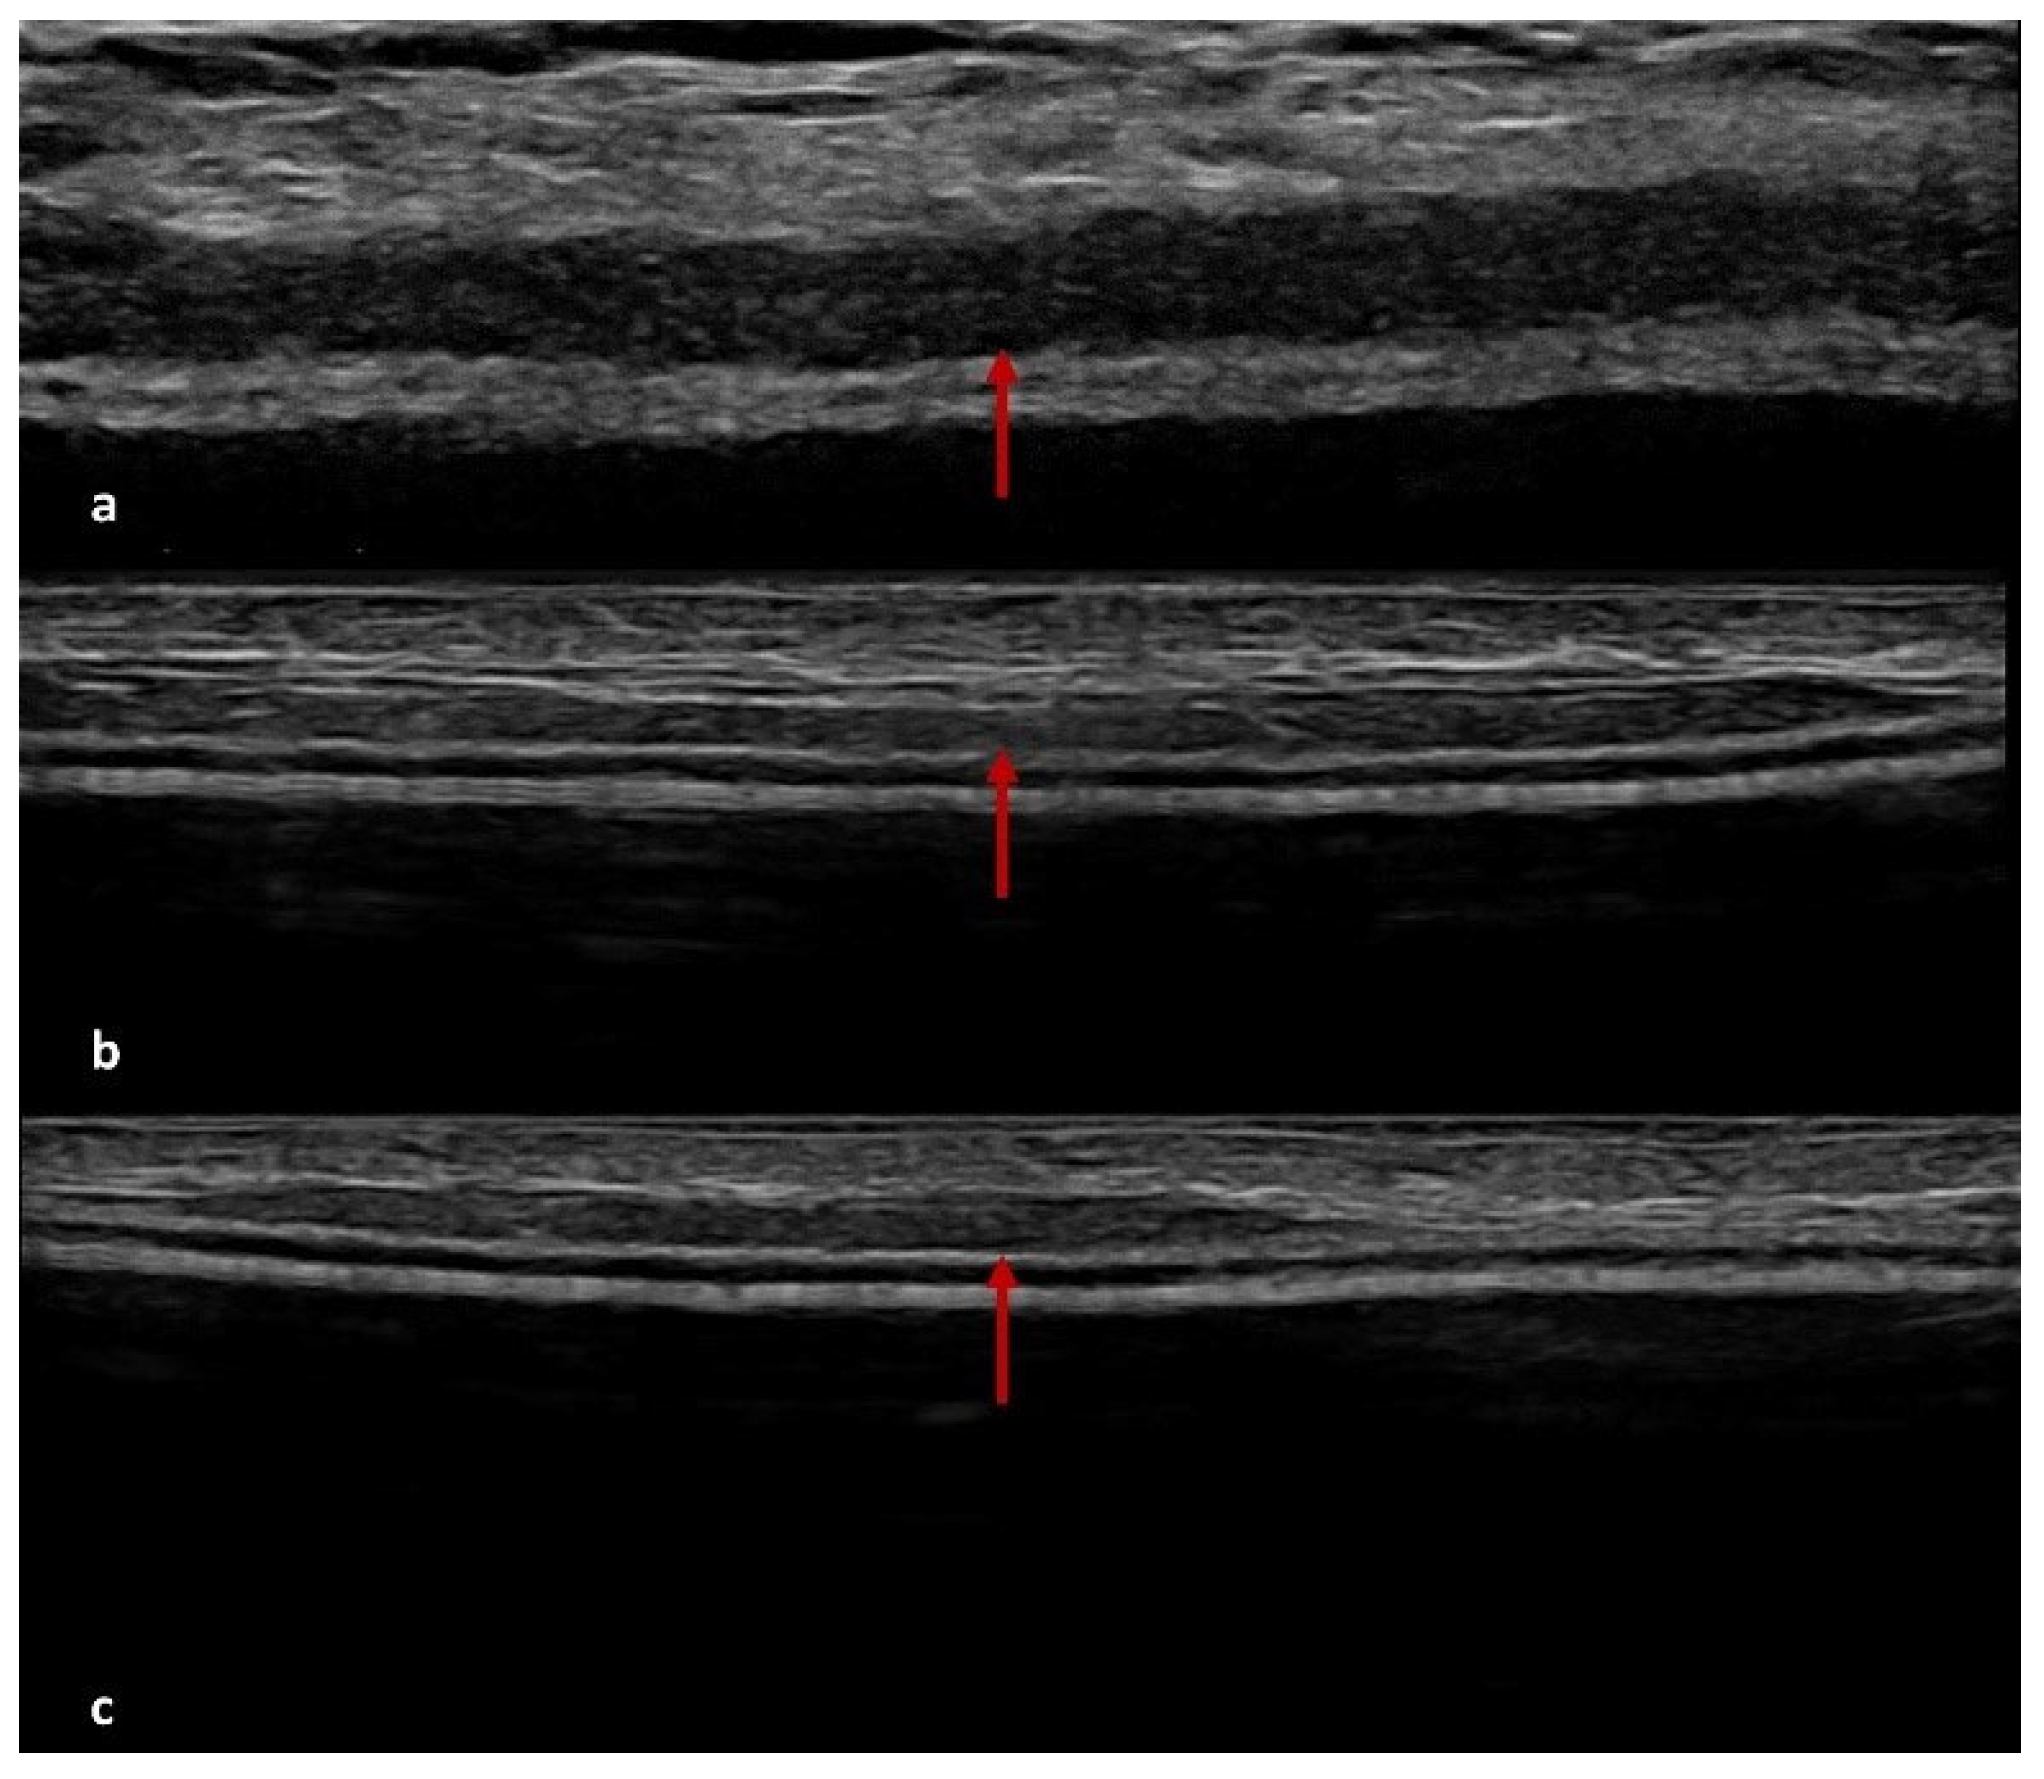

4.2. US Features of ADM

| US | Derived from pig dermis | Ten patients (16%) | Seven patients (11%) | Seven patients (11%) | Five cases of peri-capsular thickening and two cases with pseudonodular areas at T2 |